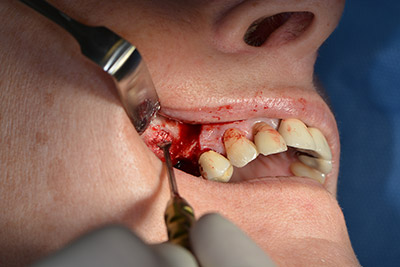

Operatives Vorgehen beim Implantieren

Die klassische Schnittführung (krestal, Entlastung bukkal) und das Präparieren des Mukoperiostlappens erlauben eine gute Übersicht.

Eine resorbierbare Membran bildet die Barriere nach bukkal und deckt das Augmentat ab. Zum Schluss wird speicheldicht vernäht. (Abb. 15 bis 19).